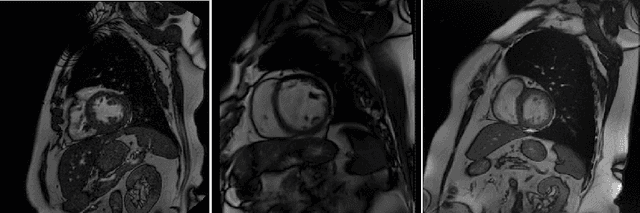

Abstract:Tracer-kinetic models allow for the quantification of kinetic parameters such as blood flow from dynamic contrast-enhanced magnetic resonance (MR) images. Fitting the observed data with multi-compartment exchange models is desirable, as they are physiologically plausible and resolve directly for blood flow and microvascular function. However, the reliability of model fitting is limited by the low signal-to-noise ratio, temporal resolution, and acquisition length. This may result in inaccurate parameter estimates. This study introduces physics-informed neural networks (PINNs) as a means to perform myocardial perfusion MR quantification, which provides a versatile scheme for the inference of kinetic parameters. These neural networks can be trained to fit the observed perfusion MR data while respecting the underlying physical conservation laws described by a multi-compartment exchange model. Here, we provide a framework for the implementation of PINNs in myocardial perfusion MR. The approach is validated both in silico and in vivo. In the in silico study, an overall reduction in mean-squared error with the ground-truth parameters was observed compared to a standard non-linear least squares fitting approach. The in vivo study demonstrates that the method produces parameter values comparable to those previously found in literature, as well as providing parameter maps which match the clinical diagnosis of patients.

Abstract:The quantification of myocardial perfusion MRI has the potential to provide a fast, automated and user-independent assessment of myocardial ischaemia. However, due to the relatively high noise level and low temporal resolution of the acquired data and the complexity of the tracer-kinetic models, the model fitting can yield unreliable parameter estimates. A solution to this problem is the use of Bayesian inference which can incorporate prior knowledge and improve the reliability of the parameter estimation. This, however, uses Markov chain Monte Carlo sampling to approximate the posterior distribution of the kinetic parameters which is extremely time intensive. This work proposes training convolutional networks to directly predict the kinetic parameters from the signal-intensity curves that are trained using estimates obtained from the Bayesian inference. This allows fast estimation of the kinetic parameters with a similar performance to the Bayesian inference.

Abstract:Purpose: Tracer-kinetic models can be used for the quantitative assessment of contrast-enhanced MRI data. However, the model-fitting can produce unreliable results due to the limited data acquired and the high noise levels. Such problems are especially prevalent in myocardial perfusion MRI leading to the compromise of constrained numerical deconvolutions and segmental signal averaging being commonly used as alternatives to the more complex tracer-kinetic models. Methods: In this work, the use of hierarchical Bayesian inference for the parameter estimation is explored. It is shown that with Bayesian inference it is possible to reliably fit the two-compartment exchange model to perfusion data. The use of prior knowledge on the ranges of kinetic parameters and the fact that neighbouring voxels are likely to have similar kinetic properties combined with a Markov chain Monte Carlo based fitting procedure significantly improves the reliability of the perfusion estimates with compared to the traditional least-squares approach. The method is assessed using both simulated and patient data. Results: The average (standard deviation) normalised mean square error for the distinct noise realisations of a simulation phantom falls from 0.32 (0.55) with the least-squares fitting to 0.13 (0.2) using Bayesian inference. The assessment of the presence of coronary artery disease based purely on the quantitative MBF maps obtained using Bayesian inference matches the visual assessment in all 24 slices. When using the maps obtained by the least-squares fitting, a corresponding assessment is only achieved in 16/24 slices. Conclusion: Bayesian inference allows a reliable, fully automated and user-independent assessment of myocardial perfusion on a voxel-wise level using the two-compartment exchange model.